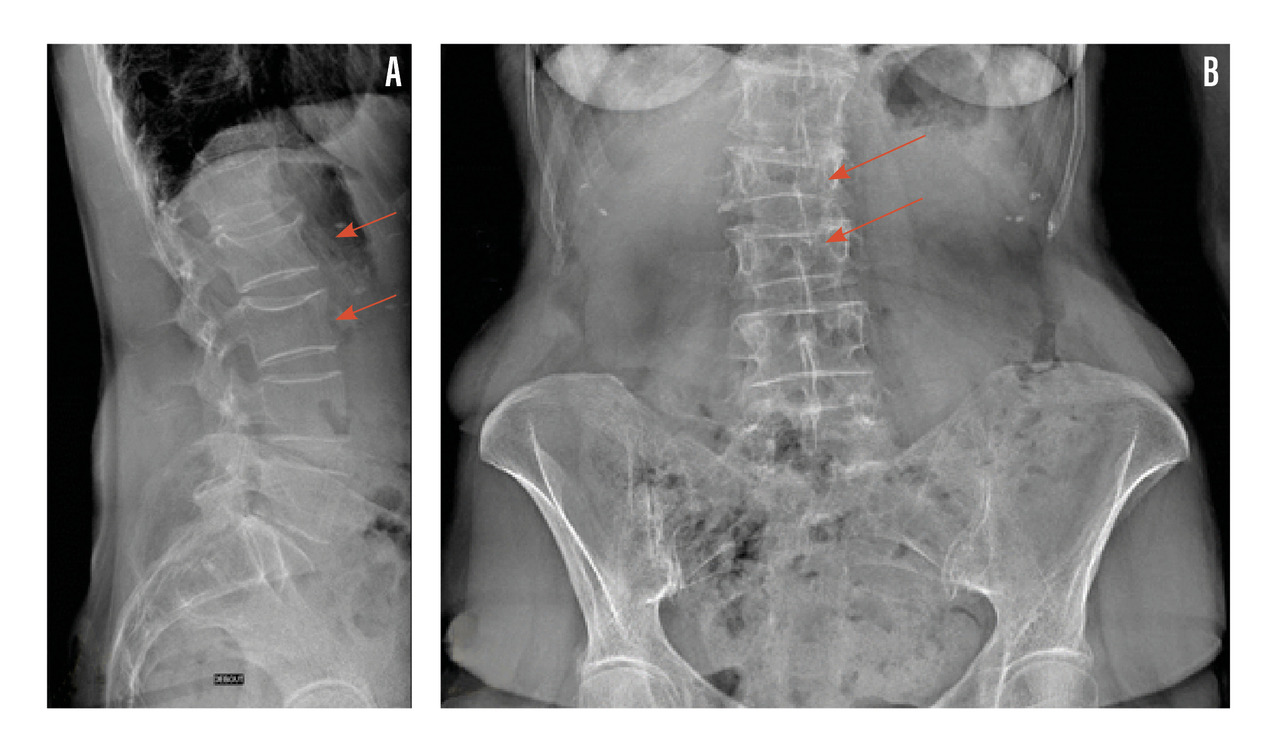

Radiographies standard

Il est indiqué de réaliser des radiographies du rachis dorso-lombaire devant des rachialgies et/ou une perte de taille supérieure ou égale à 4 cm afin de dépister une éventuelle fracture vertébrale asymptomatique (fig. 3).

Lors d’une fracture vertébrale, on recherche les signes en faveur de la nature bénigne ostéoporotique : siège de la fracture en-dessous de T3, respect du mur vertébral postérieur et de l’arc postérieur, caractère symétrique de la fracture, absence d’ostéolyse (rang B).